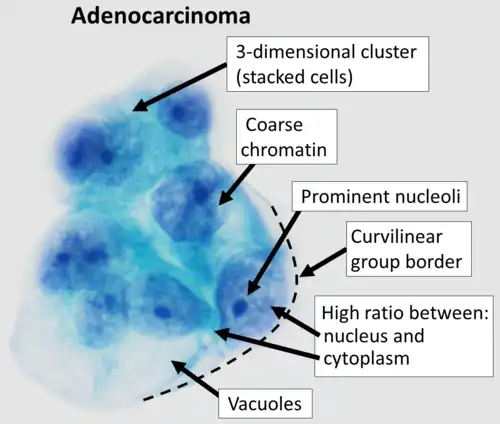

- to diagnose metastatic cancer

The color of the ascitic fluid can also be useful in analysis. Blood fluid can indicate trauma or malignancy. A milky appearance of the fluid can indicate lymphoma or malignant peritoneal ascites. Cloudy or turbid fluid can indicate possible infection or inflammation within the peritoneal cavity. Straw or light yellow colored fluid indicates more plasma-like and benign causes of peritoneal ascites.[3]